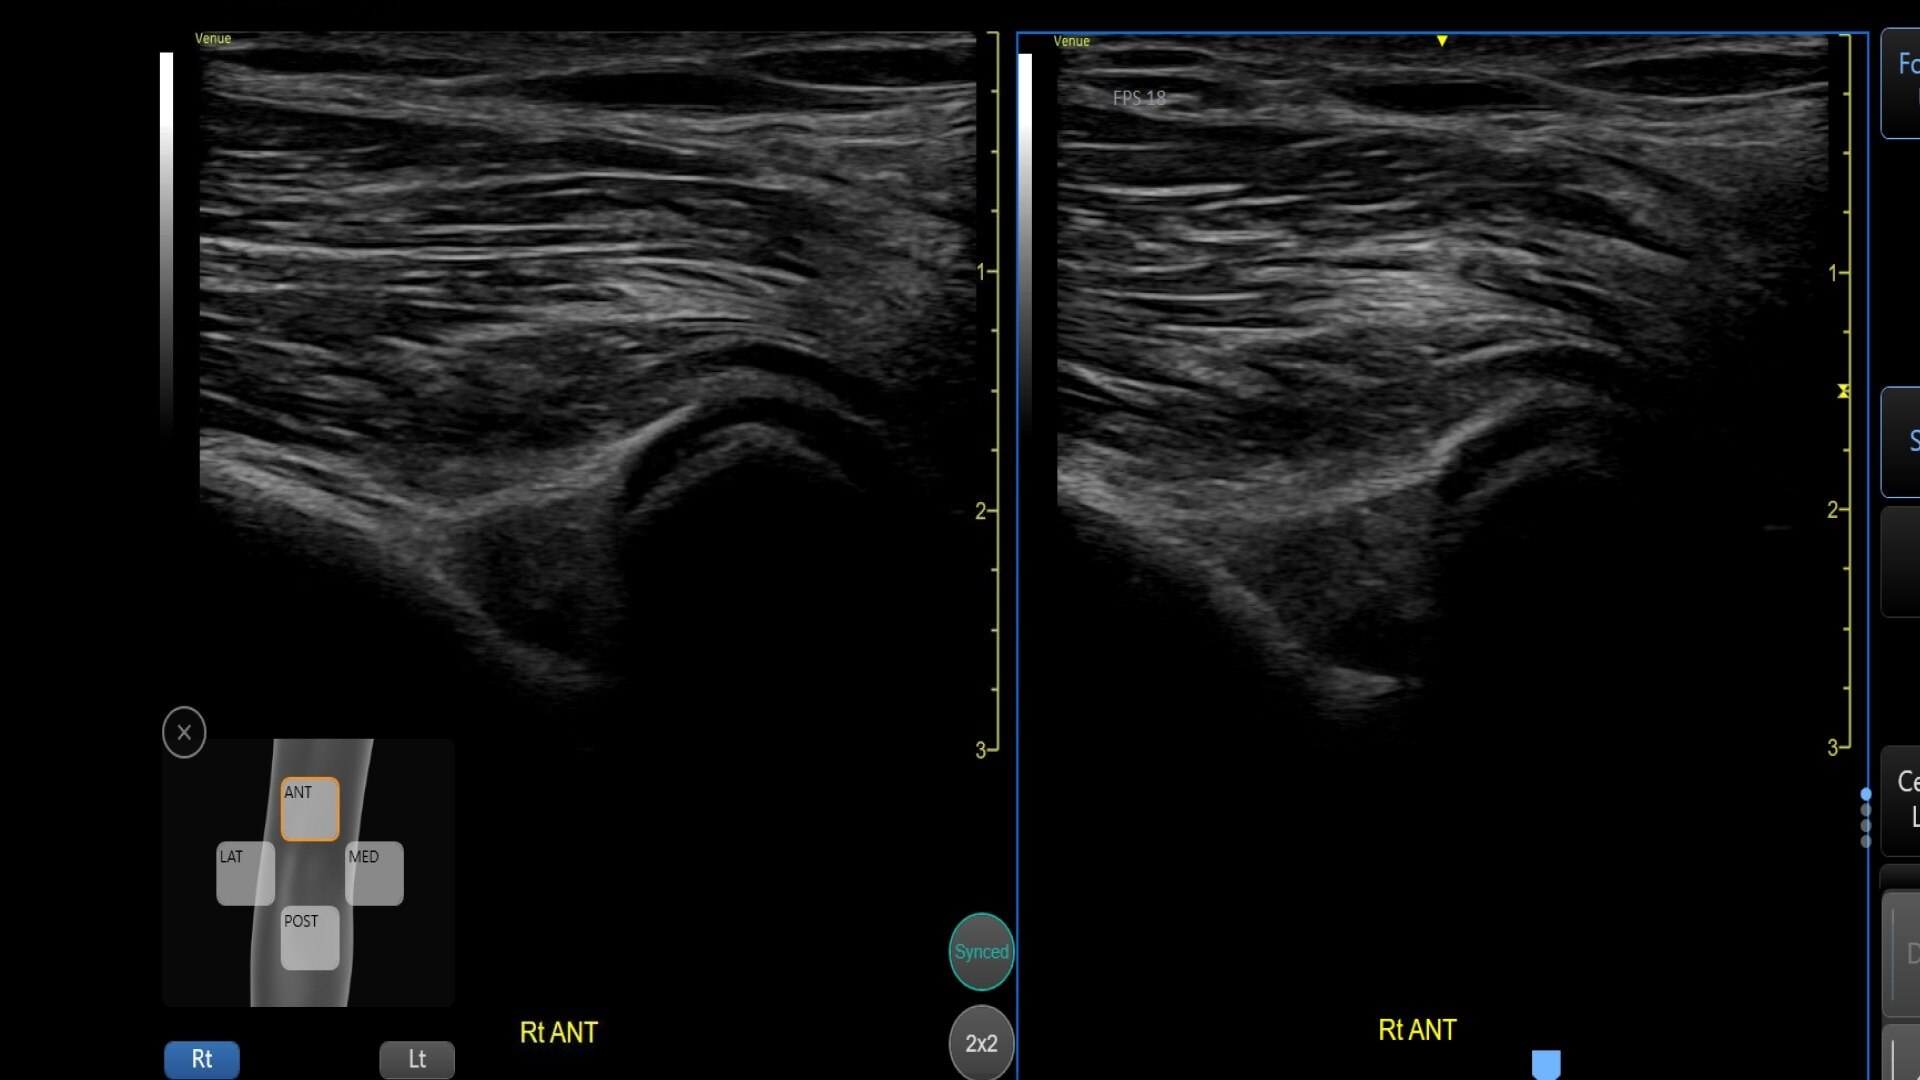

Bilateral mode: Helps you to view the opposite side of the same zone for comparison (available for Shoulder preset)

Automatically recall parameter settings with Follow Up

Delivering consistent and clear conclusions for repeated exams on the same patient, Follow Up automatically recalls parameter settings from a previous exam including comments and body patterns. It also supports monitoring of patient response to treatment over time, allowing a side-by-side view of historical and new images.